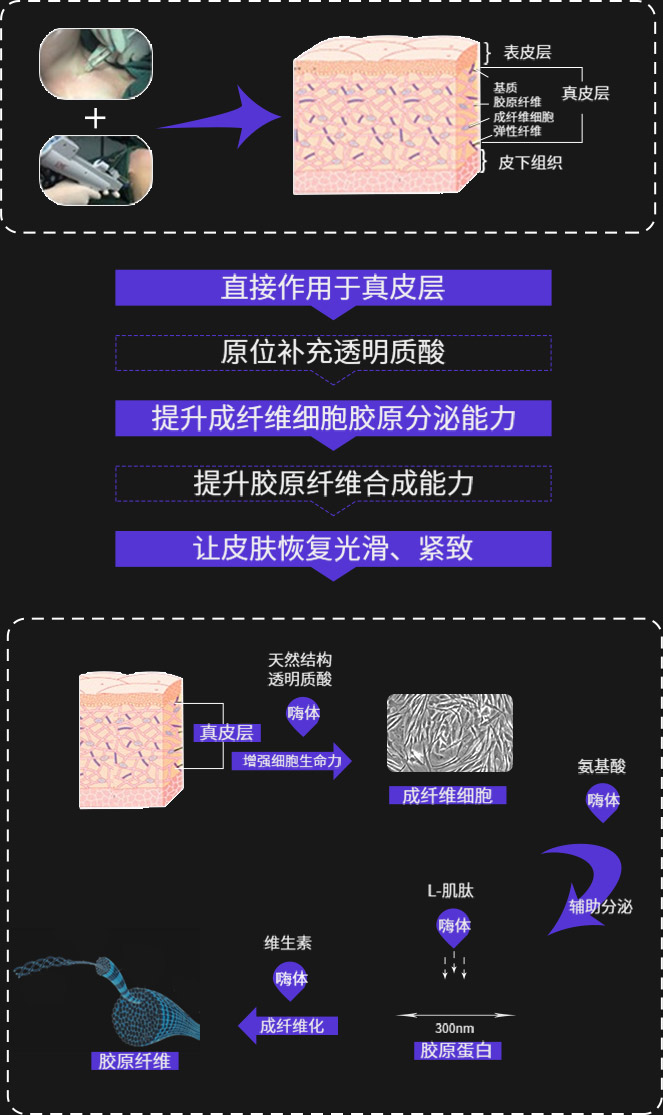

突破表皮屏障直达真皮层

STEP 1 填充颈部缺失的组织容量

以透明质酸为母液(搭载多种氨基酸、L-肌肽和维生素等)注射至真皮层满足颈部肌肤的营养补给、填充组织容量缺失

STEP 2 修复断裂的纤维组织

将营养物质及活性成分精准、定量输送到颈部皮肤中胚层修复断裂纤维组织的同时刺激皮肤新陈代谢,促进胶原蛋白再生。